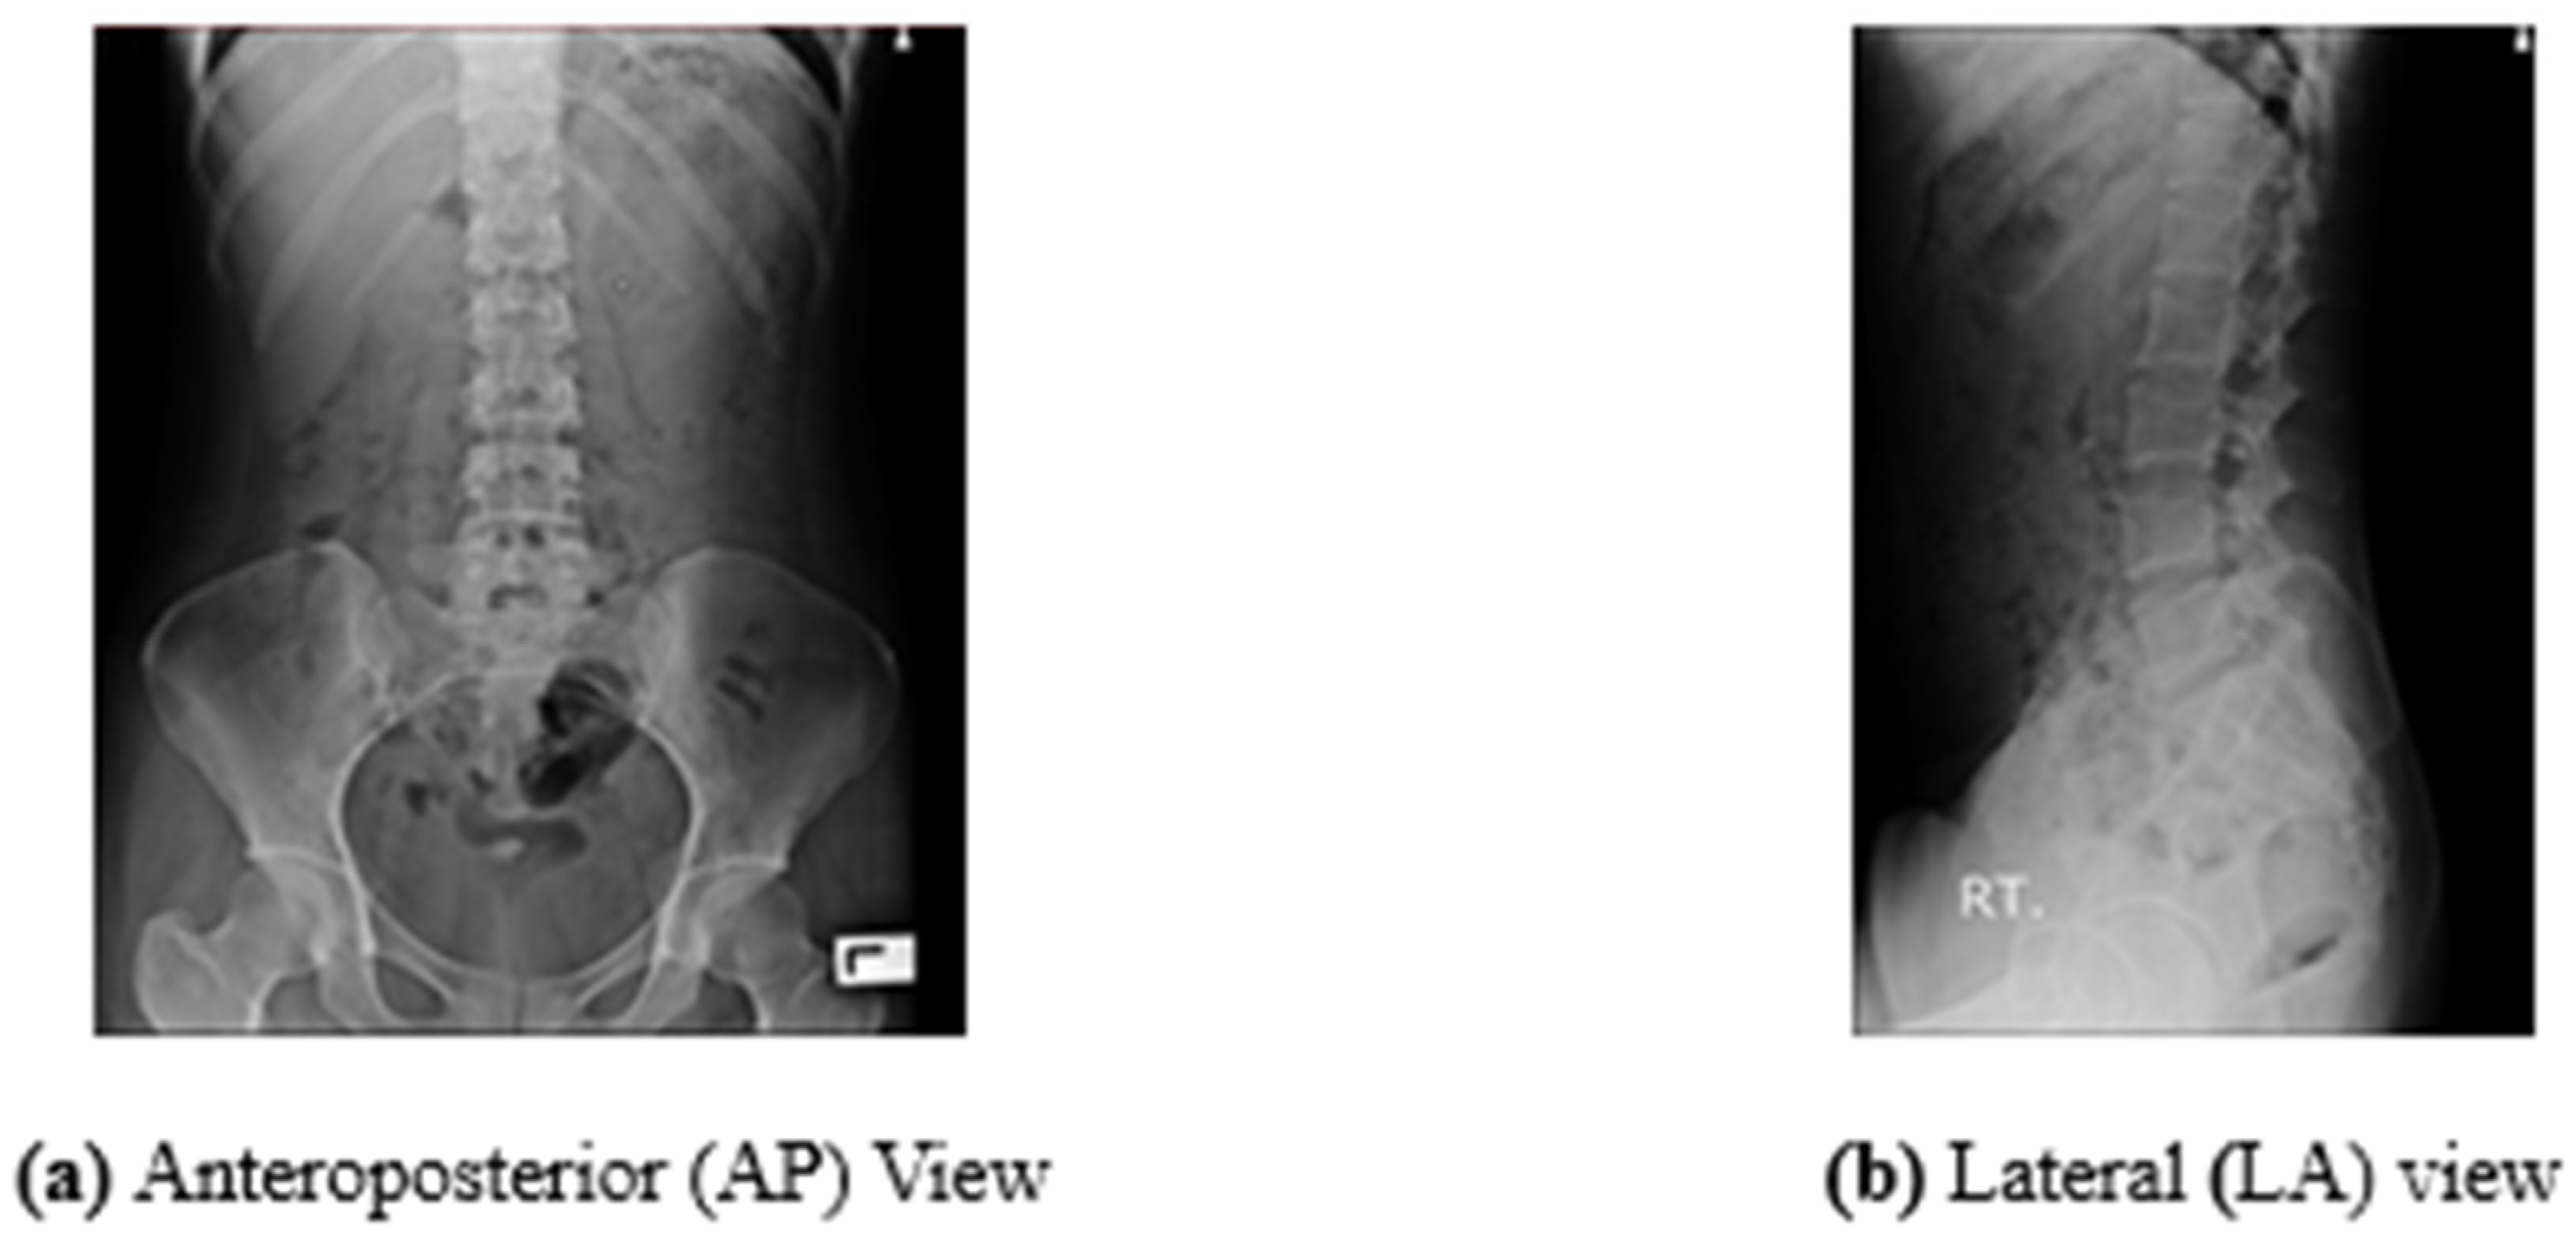

- To pinpoint the posture area of the lumbar vertebrae in environments with a low contrast. Figure 1 depicts the position of the vertebrae that must be located. Thus, each stance is observed to be difficult to execute.

| 1. | Image type | Normal X-ray (Plain film) | - |

| 2. | Body part | Lumbar spine (LSPINE) | - |

| 3. | View | AP view and LA view | - |